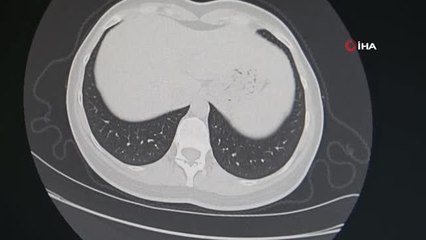

Siirt Eğitim ve Araştırma Hastanesi Sigarayı Bırakma Polikliniği, bağımlılıktan kurtulmak isteyen tiryakilere ücretsiz hizmet sunarak, kişiye özel tedavi yöntemleriyle sigarayı bırakmalarına yardımcı oluyor. brSigarayı bıraktıran poliklinik tiryakileri bağımlılıktan kurtarıyorbrSİİRT - Siirt Eğitim ve Araştırma Hastanesi Sigarayı Bırakma Polikliniği, tiryakileri bağımlılıktan kurtarıyor. Hastanede bağımlılık seviyesi ölçülüyor, ardından kişiye göre tedavi yöntemleri belirleniyor. br Siirt Eğitim ve Araştırma Hastanesi Sigara Bırakma Polikliniği, tiryakileri sigarayı bırakmaya davet ediyor. Sigara ile mücadele etmek için çaba gösterdiklerini ifade eden Sigara Bırakma Polikliniği uzmanı Dr. Büşra Eskifuruncu, tiryakilerin sigara polikliniğine gelerek bağımlılıktan kurtulabileceğini belirtti. Dr. Eskifuruncu; "Polikliniğimiz yaklaşık olarak 10 yıldır hizmet vermektedir. Bizler de burada her hafta salı günü sigarayı bırakmaya çalışan vatandaşlarımıza yardımcı olmaya çalışıyoruz.br br hbrlr1.